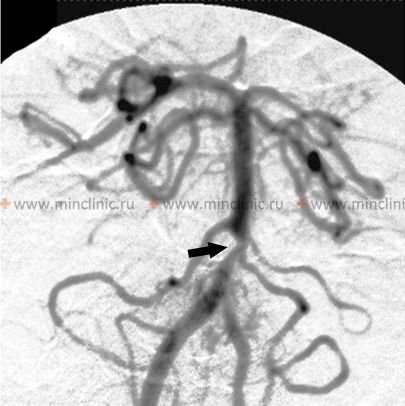

სისხლძარღვოვანი ვიზუალიზაცია: აუცილებელია სისხლძარღვოვანი დაზიანების ლოკაციის და ბუნების (სტენოზი, ოკლუზია, დისექცია, ანევრიზმა) იდენტიფიცირებისთვის [5].

- ციფრული სუბტრაქციული ანგიოგრაფია (DSA): ითვლება ოქროს სტანდარტად სისხლძარღვთა ვიზუალიზაციისთვის, უზრუნველყოფს უმაღლეს სივრცით რეზოლუციას [5, 7]. ეს არის ინვაზიური პროცედურა, რომელიც მოიცავს კათეტერის შეყვანას (ჩვეულებრივ ბარძაყის არტერიის მეშვეობით) და კონტრასტის პირდაპირ შეყვანას სამიზნე სისხლძარღვებში [7]. DSA ატარებს გართულებების მცირე, მაგრამ მნიშვნელოვან რისკს, მათ შორის ინსულტის, სისხლძარღვის დისექციის ან წვდომის ადგილის პრობლემების [1]. ის ტიპიურად გამოიყენება იმ შემთხვევებში, როდესაც არაინვაზიური ვიზუალიზაცია არადამაჯერებელია ან როდესაც იგეგმება ენდოვასკულური მკურნალობა (როგორიცაა თრომბექტომია ან სტენტირება) [5]. გარდამავალი კორტიკალური სიბრმავე ან დაბნეულობა არის იშვიათი გართულება უკანა მიმოქცევაში კონტრასტის შეყვანის შემდეგ [1].